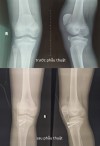

TTYT huyện Tam Nông phẫu thuật đặt lại điểm bám gân bánh chè cho bệnh nhân 13 tuổi

01:44 15/02/2022

Mới đây, người bệnh V N T (13 tuổi, Dân Quyền) nhập viện tại TTYT huyện Tam Nông trong tình trạng sưng nề gối phải, hạn chế vận động do tai nạn sinh hoạt. Sau khi thăm khám lâm sàng và cận lâm sàng, người bệnh được chẩn đoán Bong điểm bám gân bánh chè gối bên phải.